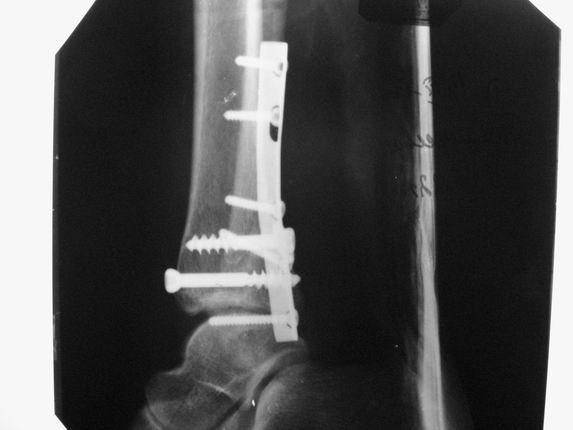

Уважаемые коллеги! Как и обещал, представляю плоды своей работы. Хвалиться особо нечем. Пошли задним

доступом сначала к м/берцовой кости, благодаря смещению линию перелома удалось сразу дифференцировать и по ней узким долотом (без молотка) мобилизовали отломки. Затем выделили задний край, там было проще пройти по линии перелома. Далее пластина по задней поверхности в дистальный отломок, винт проксимальнее пластины и дистрактором с трудом растянули отломки, ощущение было идеальной репозиции м/берцовой кости( доступен осмотр по задней и наружной поверхности), далее винты стандартно. Кстати, положение больной на боку: очень неудобно, но по-другому потом не повернуть на спину, чтобы сделать снимки в стандартных проекциях (ЭОПа нет). Затем дистрактор (два полукольца, спицы), репозиция заднего края, спонгиозный винт с шайбой, слишком проксимально, поэтому + еще один. Доступ к дельтовидной связке: рубец в передней порции, частично иссечен, шов. В общем, длительность операции 3,5 часа, а сказать, что все задуманное получилось, не могу.

Отличная, грамотная работа, поздравляю, я бы держал в гипсовой повязке до трех недель, затем разработку сустава без нагрузки, нагрузку при такой фиксации,

думаю, можно начать в 6 недель.

Все таки нужно было стянуть ДМС. Судя по снимкам остался подвывих.